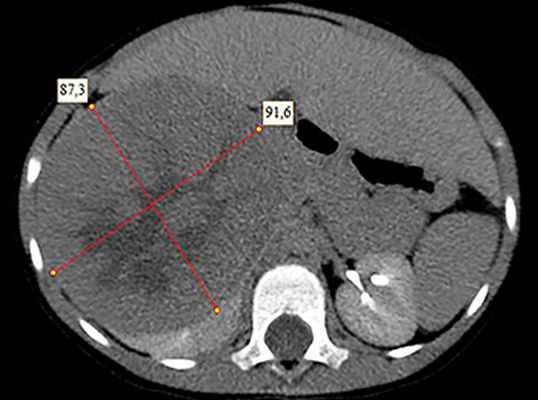

![KT 3]()

Рисунок 3. Контрольная КТ: опухоль после предоперационной химиотерапии. Ребенку проведена предоперационная химиотерапия. На 5-й неделе лечения КТ-контроль показал уменьшение опухоли в размерах до 90ґ80ґ100 мм (см. рис. 3).